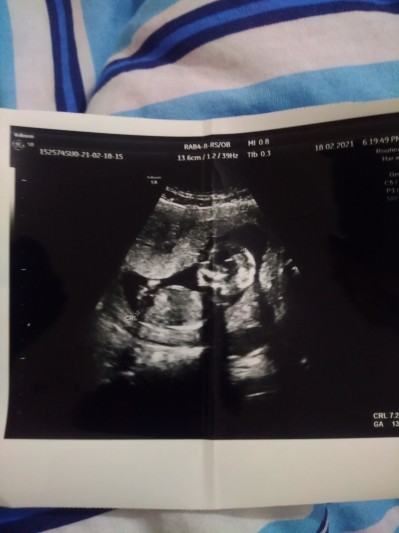

Kizlar tahmin edebilir misiniz 13 +3

Gebelik haftası 13+3

Aynıyız seninle doktorun tahminde bulunmadı mı bana erkeğe benziyor dedi

Banada erkeğe benziyor dedi ama emin olamıyorum dedi hayırlı evlat olsun da kucağımıza alalım sağ salim inşallah rabbim isteyen herkese versin

Ayni hafta ve gundeyiz doktor tahminde bulunmadimi ki bana kiza benziyor dedi tam 13 haftalikkem gitmistim

Erkeğe benziyor dedi ama ben kız hissediyordum doktor da emin değilim dedi hayırlısı inşallah sağ salim kucagimiza alırız inşallah

Erkek gibi duruyor hayırlısı olsun inşallah